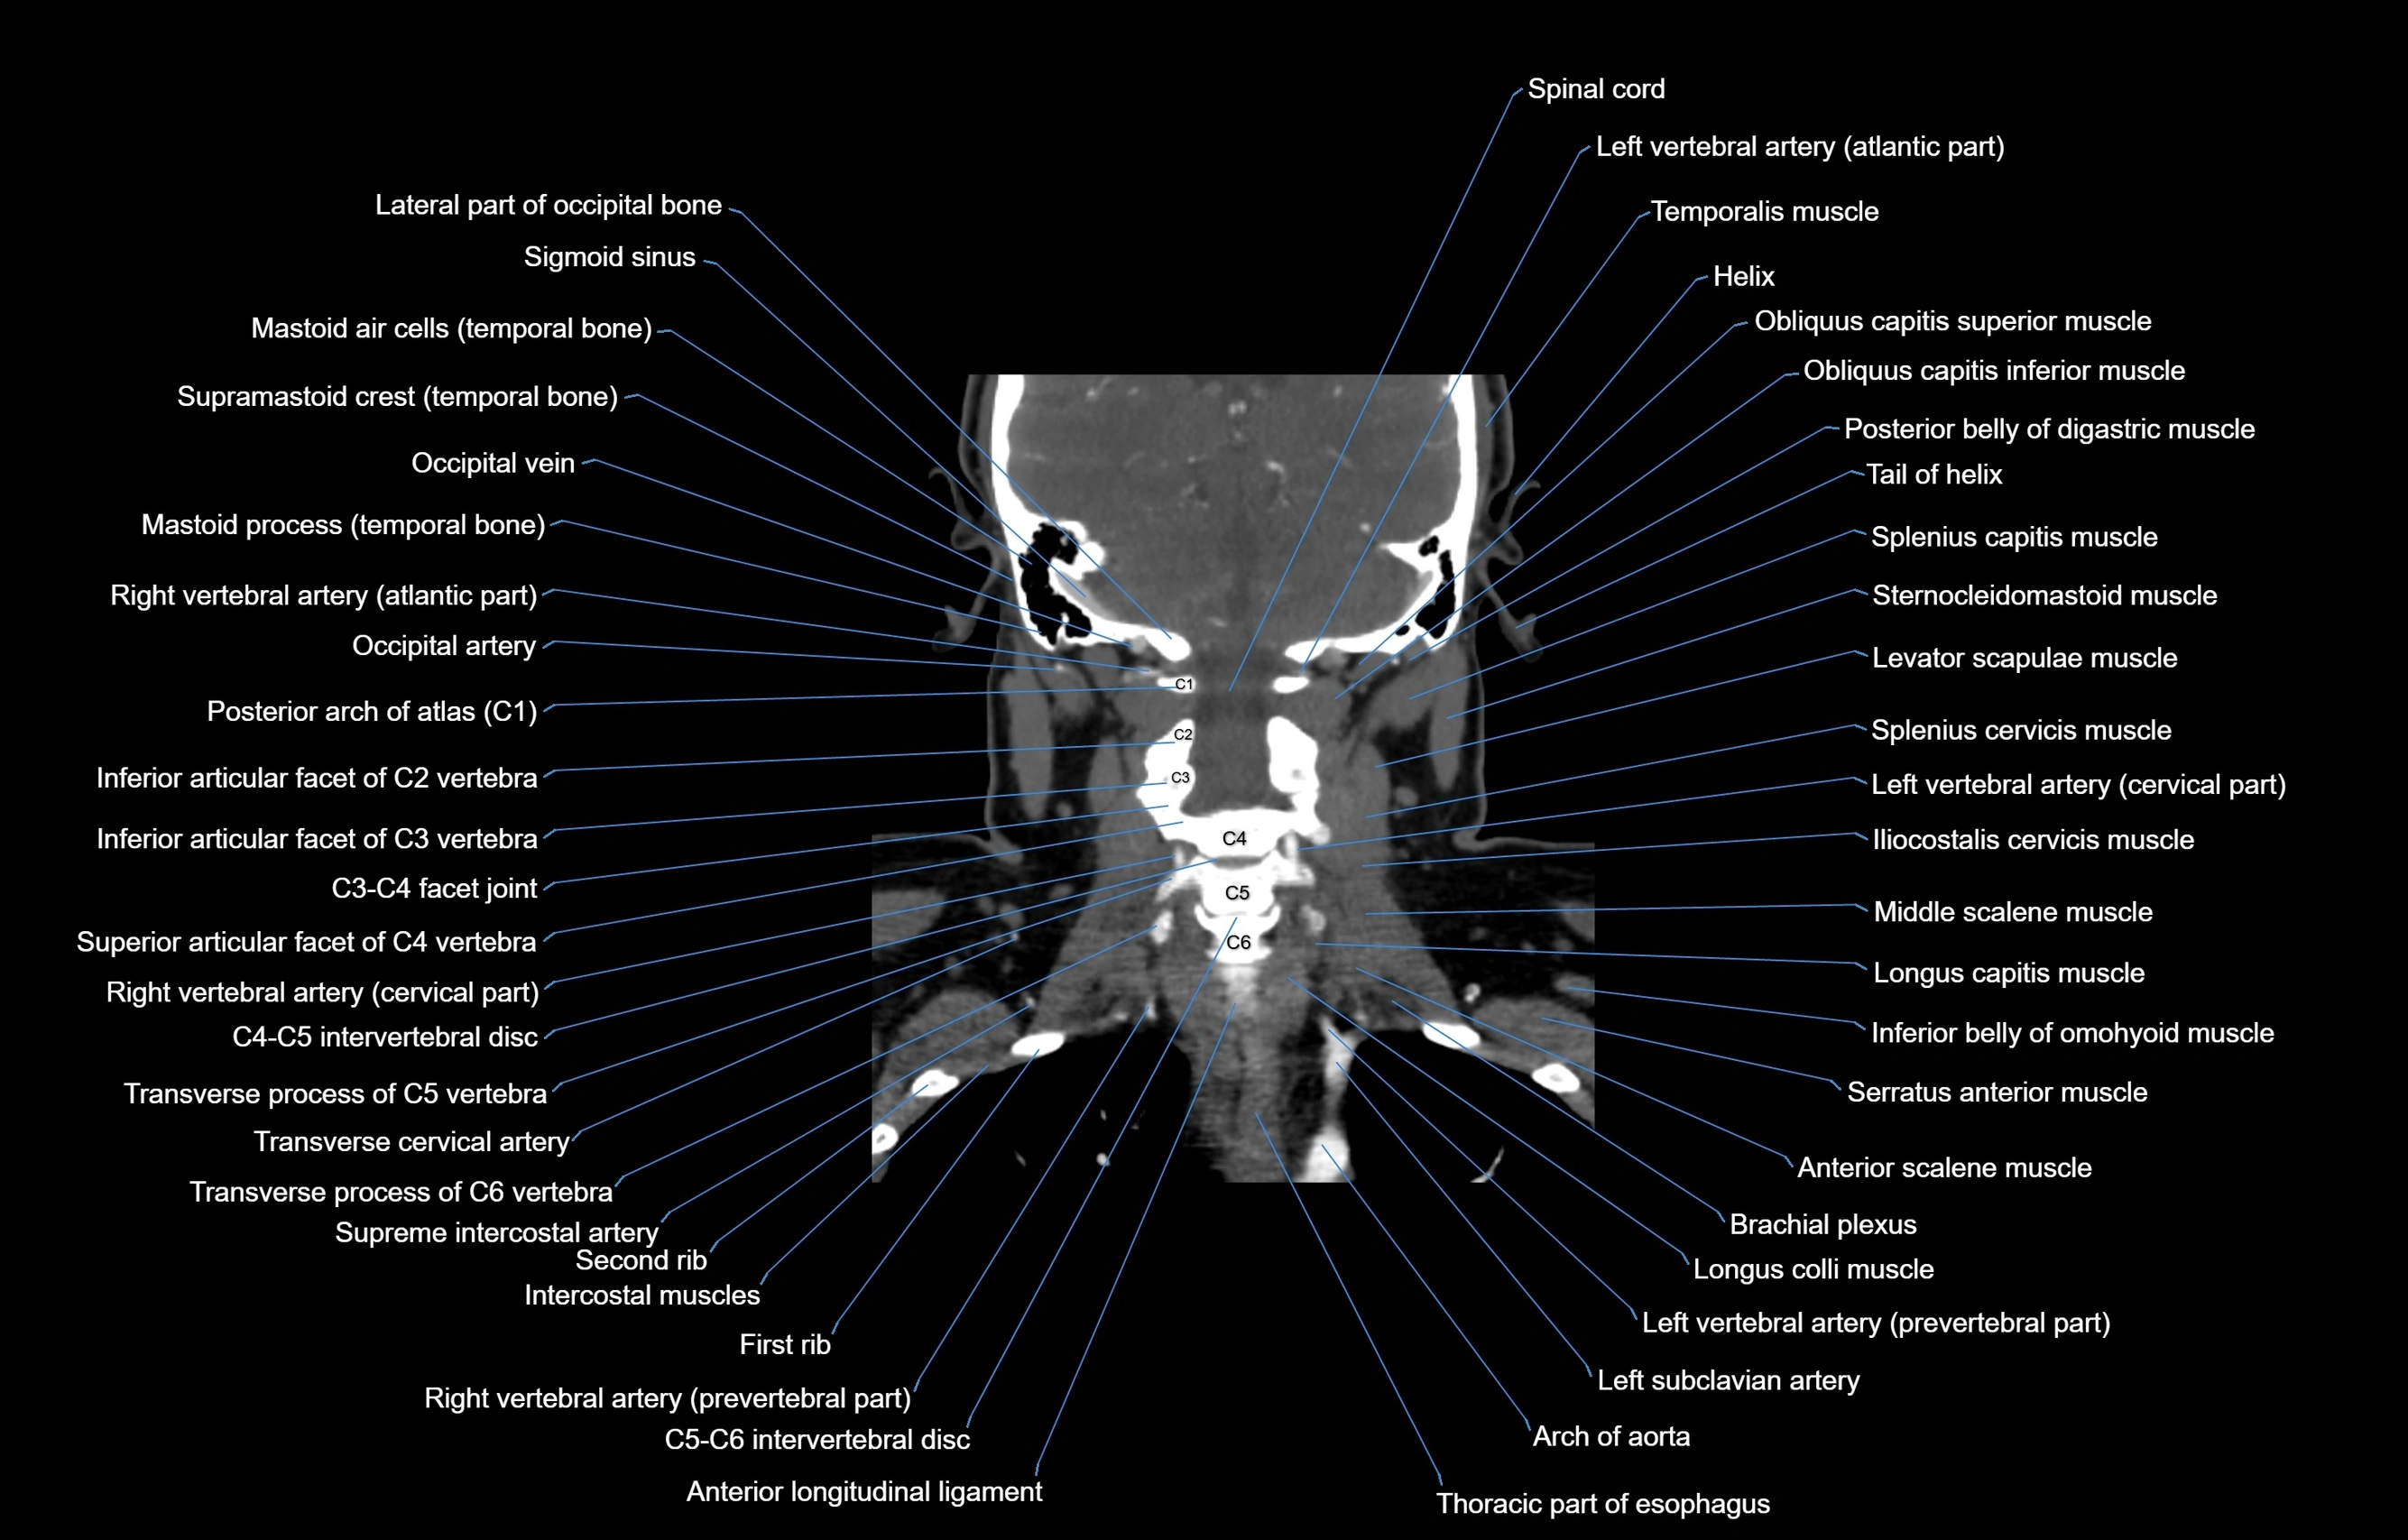

- Anterior longitudinal ligament

- Brachial plexus

- Iliocostalis cervicis muscle

- Intercostal muscles

- Left vertebral artery (atlantic part)

- Left vertebral artery (cervical part)

- Levator scapulae muscle

- Longus capitis muscle

- Longus colli muscle

- Spinal cord

- Splenius capitis muscle

- Splenius cervicis muscle

- Sternocleidomastoid muscle

- Thoracic part of esophagus

- Transverse cervical artery